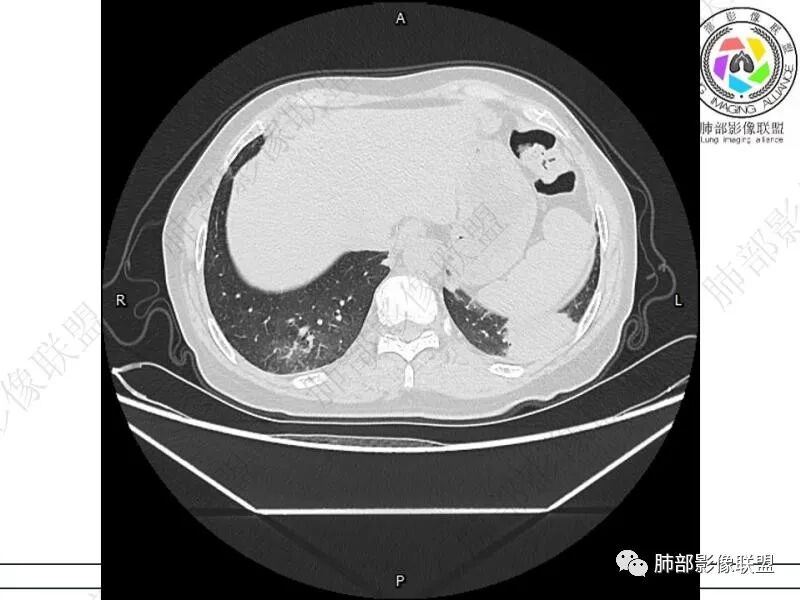

谢加平:结肠癌术后史,两肺胸膜下多发结节及斑块实变病灶,实边边界平直征(亚急性和慢性病变过程),双肺下叶后基底段胸膜下为甚,与胸膜平行特点,见支气管充气征,边缘模糊的GG0,首诊2022年11月18日肺部CT,与治疗11月28日对比,病灶未吸收,双肺下叶胸膜下病灶有侧向融合特点,综合分析符合炎性肉芽肿,隐球菌感染。

老年女性,结肠癌术后。两下肺胸膜下为主片状实变,右下肺短期复查融合且病灶长轴平行于胸膜,实变内可见支气管充气征,边缘磨玻璃晕,另两肺内胸膜下散在数枚小结节状、楔形实性灶。考虑感染性病变,隐球菌可能,鉴别肺转移。

2.影像特征:双肺胸膜下多发实性结节、磨玻璃影及实变影,胸膜下优势分布、晕征、胸膜下脂肪间隙存在,部分病灶边界平直征,有侧向融合趋势。